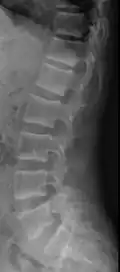

Ground glass density of the skull.[18] -